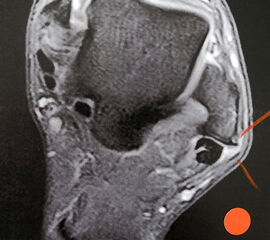

MRT

Unterbrechung des Retinakulums als indirektes Zeichen einer traumatischen Peronealsehnenluxation im MRT.

Abbildung 6

Neben der klinischen Untersuchung besitzt in der Diagnostik von Sehnenpathologie das MRT mit Kontrastmittel einen hohen Stellenwert 8910. Kontrastmittelaufnahme in die Sehne ist immer als Hinweis auf einen Riss zu werten. Weiterhin ist Flüssigkeit im Sehnengleitlager oder die Aufnahme von Kontrastmittel in das Sehnengleitgewebe ein indirektes Zeichen einer Sehnenpathologie.